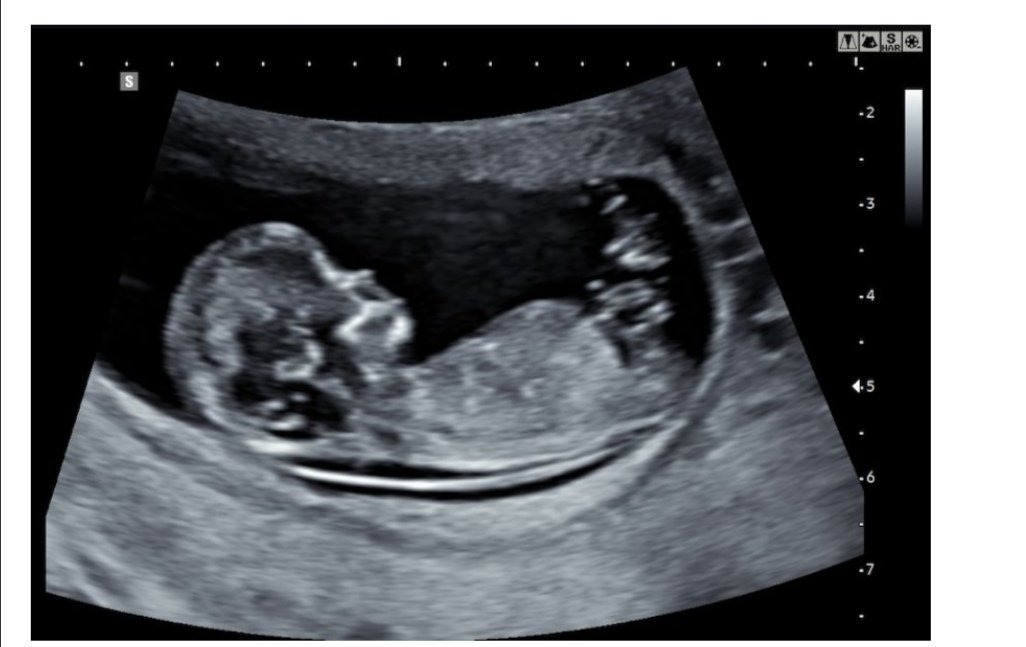

Tansu Məmmədzadə: Hamiləlikdə 1-ci trimestrin önəmindən DANIŞDI

Millixəbər.az-ın “Həkimlə Biz” rubirkası “Ömür” Klinkasınının direktoru, həkim ginekoloq Tansu Məmmədzadənin tibbi maarifləndirici fikirlərini sizlərə təqdim edir.

İstəkli izləyicilər, əziz xanımlar bu gün haqqında danışacağım mövzu ilk trimestrə aid olduqca əhəmiyyətli mövzudur.

Hamiləlikdə 3 trimestr var: 1-ci, 2-ci və 3-cü trimestr hamiləlik .Birinci trimestr 12 həftəyə kimidir, 2-ci trimestr 12 həftədən 24 həftəyə kimidir və 3-cü trimestr isə 24 həftədən doğuşa qədər olan dönəmdir.

İlk trimestr çox önəmlidir. Beləki, xanımlarımız,gələcək analarımız ilkin hamiləliyin əlamətlərini özlərində görəndə əvvəlcə hamiləlik testi edirlər,hamilə olduqlarını bildikdən sonra isə təəssüf ki, boş yanaşırlar,həkimə getməyi düşünmürlər. Amma birincisi hamiləlik testi çıxan kimi ultrasəs müayinəsinə gəlmək lazımdır və qanda beta HCg dediyimiz analiz deyerini vermək lazımdır. Bunu da ona görə etmək lazımdır ki çox hallarda ektopik, yəni uşaqlıqdan kənar hamiləlik kimi vəziyyətlərlə qarşılaşa bilərik ki, bu zaman da hamiləlik testi pozitiv,yəni iki xətt çıxır. Amma ki xanımlarımız vaxtında qanda beta HCg analizini vermədən, yaxud da vaxtında ultrasəs müayinəsinə düşüb uşaqlıqda yəni endometriyumda döl kisəsini görmədən davam etsələr təbii ki, uşaqlıqdan kənar hamiləlikdirsə bu vaxt onlar heç zaman onu aşkarlaya bilməyəcəklər və bunun da nəticəsində təəssüflər olsun ki, gecikdirilmiş bir vəziyyətdə, məcbur şəkildə əməliyyat icra etməli oluruq. Ona görə bu vəziyyətlərə gəlib çıxmamaq üçün,əməliyyatla qarşılaşmamaq üçün biz məsləhət görürük ki hamiləlik olan kimi mütləq şəkildə həkimə müraciət olunsun.

Beləki hamiləliyin başlanğıcı ilə bağlı 1-ci trimestrin önəmindən danışdıq.1-ci Trimestrin önəmininin də əsası təbii ki ürək döyüntüləridir. Bilirsiniz ki, inkişafdan qalmalar ən çox bu həftələrdə olur. Bunu da nəzarətdə saxlamaq üçün mütləq şəkildə həkimə müraciət etmək lazımdır.Heç bir xanım deyə bilməz ki mənim hamiləlikdə problemim yoxdur, təbii ki, istəmərik də olsun. Amma hər bir halda ehtiyyatı saxlamaq və həkim nəzarətində olmaq lazımdır. 1-ci Trimestrin ən önəmli skrininq dediyimiz protokola görə və dünya üzrə qəbul olunmuş qayda və qanuna görə skrininq testlər keçirilir hamiləlik boyunca. O skirenninqlərdən biri də hamiləliyin 11-ci 13-cü həftəsi arasında keçirilən ikili tarama testi dediyimiz qüsur analizidir. Bir neçə dəfə hamilə olmuş xanımlarımızın bu haqda məlumatı var.

Ultrasəs müayinəsində ənsə qalınlığı dediyimiz bir ölçü var. Ənsə qalınlığı üzərindən həm də qannan analiz verərək biz ikili tarama testini icra edirik. Bu ikili tarama testinin nəticəsi də təbii ki yenə heç bir şey tibbdə də, heç bir sahədə də bizə 100 faizlik deyil,ən yüksək 90 faiz məlumat verir. Qüsurları ortaya çıxarmağımızda və yaxud da inkar etməyimizdə bizə yardımçı olur. Hər kəsin bildiyi və eşitdiyi Daun sindromu deyilən bir xəstəlik var. Genetik xəstəlikdir. 21 xromosomun deffekti üzrə ortaya çıxır və normalda 46 xromosom ortaya çıxmalıdırsa belə xəstə uşaqlarda 47 xromosom olur genetik kodunda. Bu da təbii ki gələcək valideyn üçün çox önəmli bir nüansdır. Valideyn hər bir halda bunu bilməlidir.Bəzi valideynlər varki istəmir,bəzi valideynlər varki yenə də hər bir halda uşağı dünyaya gətirəcəm deyir.

Bu tarama testin,1-ci trimestrin önəmini mən vurğulamaq istəyirdim gələcək analar üçün. Çünki belə bir situasiyalarla çox tez-tez qarşılaşırıq.